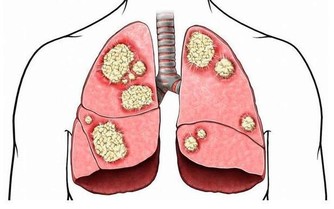

大魚大肉過後,是否有不斷放臭屁、便祕、肚子悶痛或大便變細等症狀?如果一段時間後就恢復正常,就不必太擔心;如果狀況持續1個月以上,可能是大腸病變的前兆,應小心為妙。

據衛生署統計資料,大腸癌(包括直腸癌及結腸癌)占國人癌症死因的第3名,而且10年前的平均罹患年齡為62歲,最近降低為54歲,在美國南加州大學擔任副教授的陳昌平醫師更預測:「10年後,年齡層會降到45歲左右,因此民眾不能不注意。」

便祕、腹痛 大腸癌前兆

陳 昌平說明大腸癌的成因:「簡單說,是先有便祕,接著產生息肉,再病變成大腸癌。」大腸是由升結腸、橫結腸、降結腸及乙狀結腸等所構成,左側的大腸管徑比右 側大腸窄,當有腫瘤發生時,就會出現腸阻塞而引起便祕、腹脹甚至腹痛的情形。因為糞便大多在左側的結腸成形,因此如果阻塞的狀況嚴重的話,所排出的糞便就 會有時還會參雜血絲, 嚴重到便祕及解血便情形。

陳昌平認為,大腸癌的成因與飲食最有關係,其次是遺傳,因此經常大魚大肉或有家族病史者,一定要 每年接受檢查,及早發現及早治療。許多研究皆顯示,攝取過多的動物性脂肪會增加罹患大腸癌的機會,因此應多吃高纖食物,食物纖維有助於吸收腸內水分,使糞 便體積增大,刺激腸子蠕動,方便排泄,避免便祕且縮短致癌物質留在腸內的時間,降低罹癌機率。